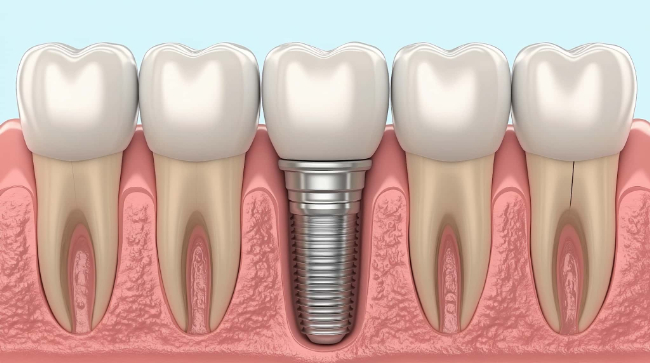

インプラントとは、失った歯の機能を回復するために、顎の骨に人工の歯根を埋め込み、その上に人工の歯を装着する治療法です。一般的には、チタン製のインプラント体を顎の骨に埋め込み、その上にオールセラミックやジルコニアなどでできた人工歯を取り付けます。

インプラントの大きな特徴は、天然の歯と同じようにしっかり噛めるようになることです。入れ歯やブリッジと異なり、周囲の健康な歯に負担をかけずに独立した人工歯を作れるため、審美性や機能性にも優れています。

また、しっかり顎の骨と結合することで安定性が高く、適切にケアをすれば長期間使用することも可能です。